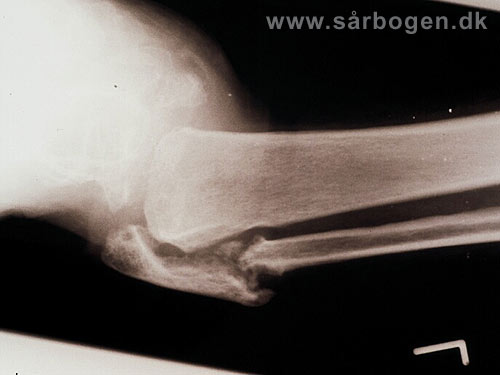

Charcot i ankel (rtg...